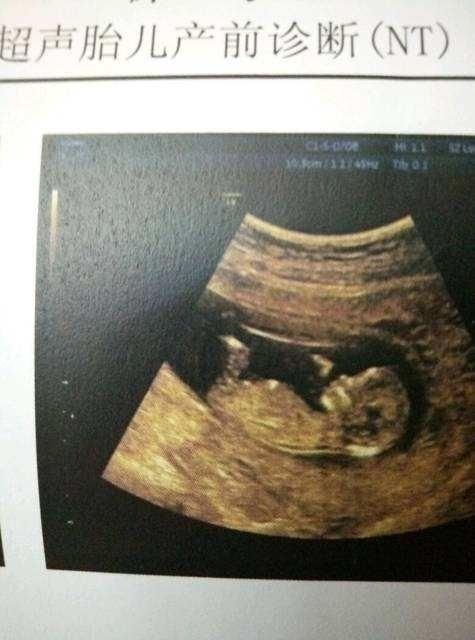

NT也是排畸产检项目中的一种,又被称之为早期唐筛。主要是通过扫描胎儿的颈部透明带的厚度来评估胎儿是否患有唐氏综合征的风险。

如果诊断出胎儿的NT值小于2.5毫米的话属正常,如果诊断出胎儿的NT值大于2.5毫米的话就属于唐氏综合征高风险了,医生可能会建议孕妈妈做无创或者直接做羊水穿刺继续确诊,以更准确地判断胎儿的发育情况。